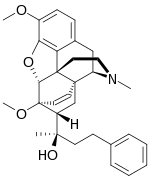

Oripavine derivatives

Thienorphine

- 7-PET

- Acetorphine

- Alletorphine (N-allyl-noretorphine)

- BU-48

- Buprenorphine

- Buprenorphine-3-glucuronide

- Cyprenorphine

- Dihydroetorphine

- Etorphine

- Homprenorphine

- 18,19-Dehydrobuprenorphine (HS-599)

- N-cyclopropylmethylnoretorphine

- Nepenthone

- Norbuprenorphine

- Norbuprenorphine-3-glucuronide

- Thevinone

- Thienorphine

Structures

| Oripavine derivatives | ||||

|---|---|---|---|---|

7-PET 7-PET |

Acetorphine Acetorphine |

Alletorphine Alletorphine |

BU-48 BU-48 |

Buprenorphine Buprenorphine |

Cyprenorphine Cyprenorphine |

Dihydroetorphine Dihydroetorphine |

Etorphine Etorphine |

Homprenorphine Homprenorphine |

18,19-Dehydrobuprenorphine 18,19-Dehydrobuprenorphine |

N-cyclopropylmethylnoretorphine N-cyclopropylmethylnoretorphine |

Nepenthone Nepenthone |

Norbuprenorphine Norbuprenorphine |

Thevinone Thevinone |

Thienorphine Thienorphine |